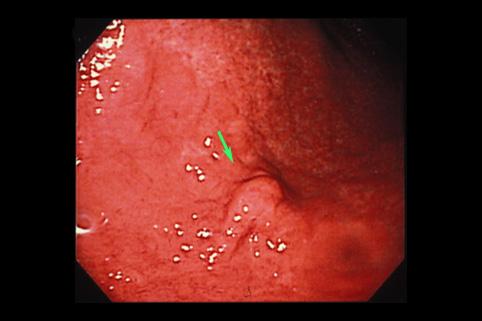

점막하 종양의 형태를 나타낸 호산구성 육아종(위 아니사키스 의심)

[Image-ID:9436]

기생충질환/아니사키스

위(부위)/전정

15~19